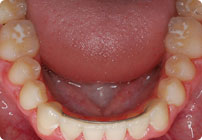

Antes

Caso: 11 años

Adolescente: Clase II

Mordida Cruzada Posterior

Sin extracción

Sin uso de expansores

6 alambres superiores

5 alambres inferiores

Sin uso de elásticos

Retenedores: Interior Fijo de TMA y Hawley en superior

Tiempo de tratamiento: 14 Visitas